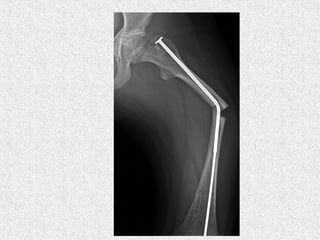

ļ‚ž Sofield & Millar

ļ‚” Multiple osteotomies

ļ‚” Realignment

ļ‚” Medullary nail-solid

ļ‚ž Indication

ļ‚” Deformity correction

ļ‚ž 4 main types are developed

ļ‚”Bailey-Dubow

ļ‚”Sheffield

ļ‚”Fassier-Duval

ļ‚”Interlocking telescoping rods

ļ‚ž These rods have a female hollow nail anchored

in the proximal epiphysis of the long bone and a

male solid nail anchored to the distal epiphysis.

They are elongated as the child grow. So, less

revision rates compared to solid

ļ‚ž Rod diameter

ļ‚” Larger diameter gives more stability but causes bone loss

around the rod

ļ‚”Therefore, thinner rods are recommended acting as

internal tutor and not replacing the bone

ļ‚”Leaving 2 mm around the rod in any plan is a safe

method

ļ‚ž Rod length

ļ‚” Pre-operative templates are essential taking into account the

osteotomies needed to straighten the bone

ļ‚”Measure the length (L) between greater trochanter

and distal growth plate

ļ‚”Female rod length is (L) - 7 mm

ļ‚”Male rod length is (L) + (10-15) mm